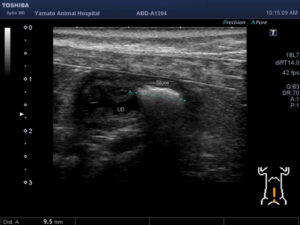

ワンちゃんが乳腺にできた複数のシコリを気にされて来院されました。bilateral mastectomyで対応しました。摘出後の病理組織検査の結果は、「R3-4間腫瘤:乳腺癌(複合型)」でそれ以外は「良性乳腺混合腫瘍」でした。無事元気に退院し、その後再発もなく経過は良好です。よかったね。